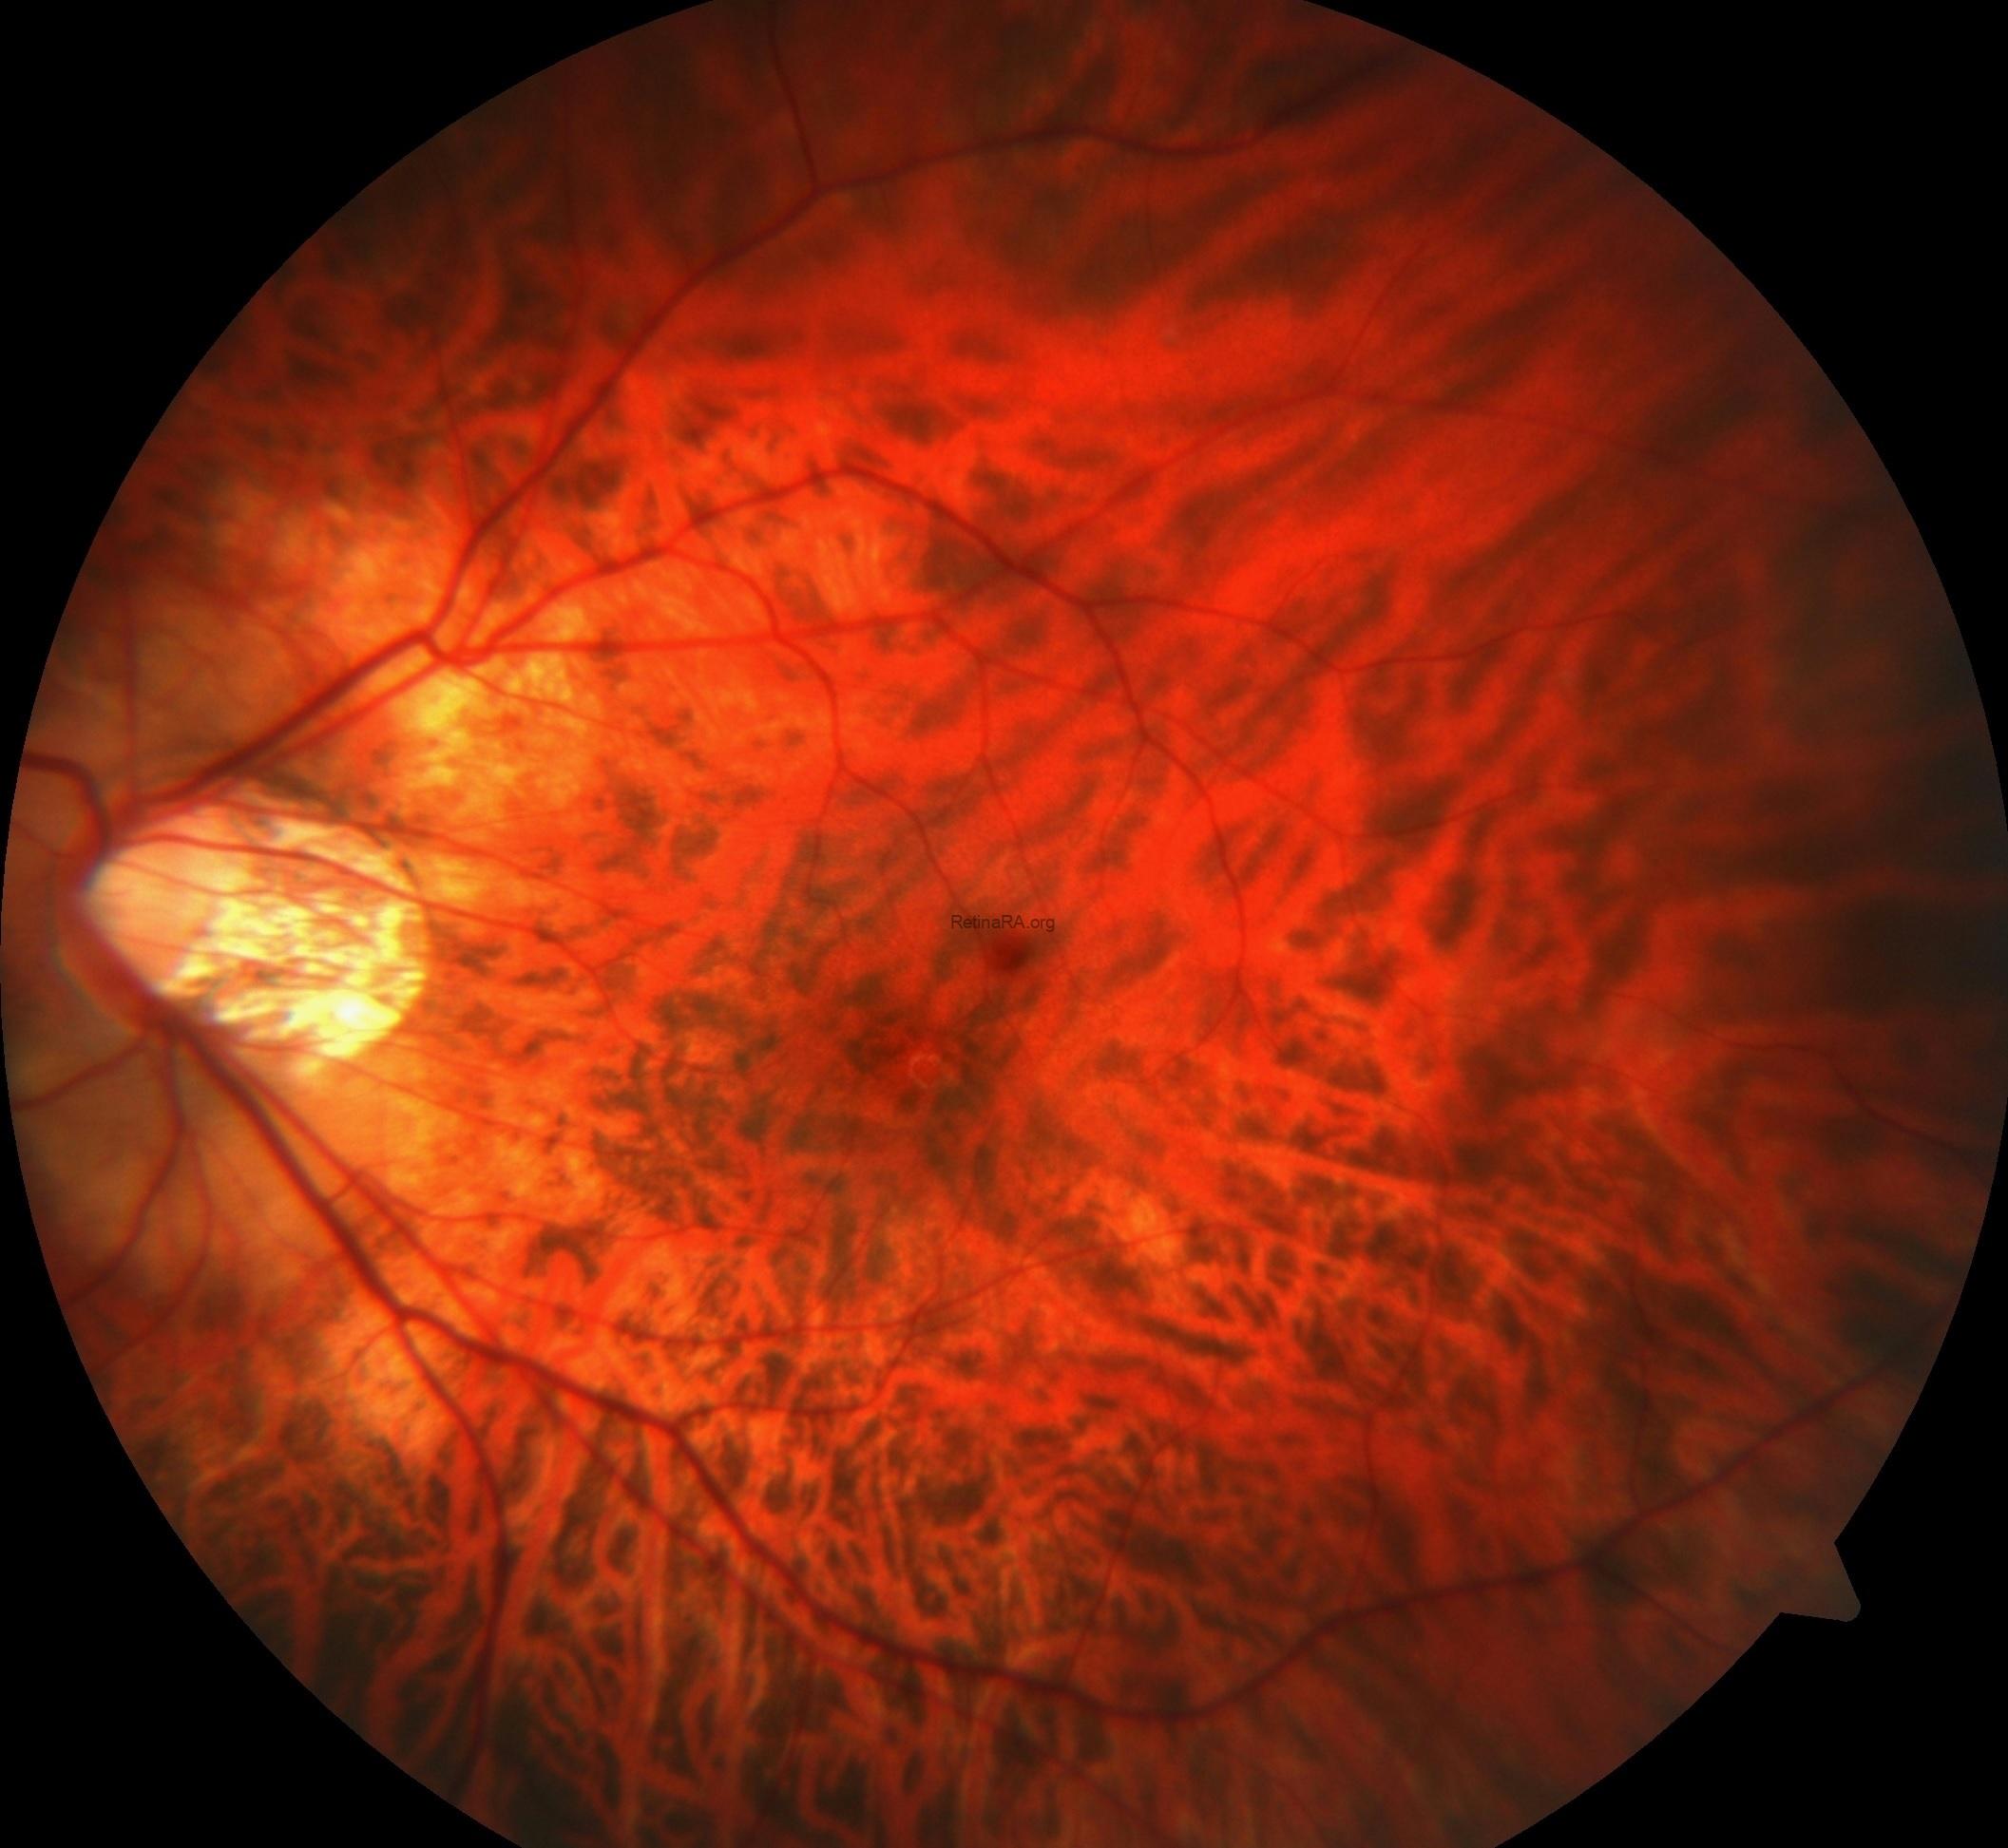

Dilated fundus examination of the right eye showed tilted disc, peripapillary and chorioretinal atrophy as well as macular scar, while the left eye exhibited aa well-defined, yellow-orange lesion located inferiorly along the border of the myopic crescent in additon to tilted disc, peripapillary and chorioretinal atrophy.

Fundus fluorescence angiography showed scar staining without leakage in the right eye, while the peripapillary lesion in the left eye appeared as hypofluorescent in the early stages of angiography and hyperfluorescent without leakage in the late stages.

Peripapillary intrachoroidal cavitation is a yellow-orange lesion which located at the outer border of the myopic conus. First described as a localized detachment of the retinal pigment epithelium, its intrachoroidal location was later revealed, justifying its current name. It can be seen with other myopic complications such as posterior staphyloma, but its pathogenesis is not still clear to. Although it has been considered a benign condition, most eyes with intrachoroidal cavitaiton demonstrate visual field defects leading to diagnostic uncertainty as these deficits resemble those seen in glaucomatous eyes. With the advances in optical coherence tomography, high optic nerve sheath traction forces during eye movements in highly myopic eyes have been suggested as promoters of intrachoroidal cavitaiton.